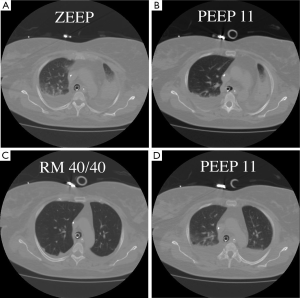

Recruitment is a dynamic process of re-opening unstable airless alveoli through an intentional transient increase in transpulmonary pressure. This process can be accomplished through a variety of methods that will be discussed below. The rationale for the use of RMs in ARDS is to promote alveolar recruitment, leading to an increased end-expiratory lung volume and thus a switch from the so-called ‘baby lung’ to a ‘normal lung’ (2). The concept of the baby lung originated from observations on the first computed tomography (CT) scan images obtained in ARDS patients, which showed that densities were preferentially distributed in the dependent lung regions, whereas the non-dependent lung regions were relatively spared. This view contrasts with the common belief, derived from anteroposterior imaging, that ARDS homogeneously involves the entire lung parenchyma. Quantitative analysis of the CT scan showed that the pathoanatomy of the ARDS lung is not homogeneously distributed. Instead, it is the sum of regions that are non-aerated and poorly aerated and of regions that are normally (or almost normally) aerated. Only a small proportion of the lung is ventilated, and this small lung, the baby lung, has to fulfil the physiological needs of an adult body. When used at moderate levels, with a plateau pressure below 30 cmH2O, the application of positive end-expiratory pressure (PEEP) is inefficient in recruiting the lung. Our group showed in a CT scan study (3) that PEEP does not increase the gas volume in the poorly and non-aerated lung, but when an RM is performed, the same level of PEEP is sufficient to keep the lung open (Figure 1). Switching from a baby lung to a normal lung can be done in two ways only—performing RMs or waiting for an improvement in lung function, which leads to a decrease in transpulmonary pressure required to open the lung. Waiting for such an improvement may be long, and mechanical ventilation may increase lung injury during this time.

The other point is the type of ARDS. In a large CT scan study, Gattinoni’s group presented interesting data on recruitability (15). In this study, CT showed that the percentage of potentially recruitable lung varied widely among patients with ARDS, from a negligible fraction to more than 50% of the total lung weight. Furthermore, the percentage of potentially recruitable lung was itself highly correlated with the overall severity of lung injury. This amount of recruitable lung could be assessed with two CT scans at two different levels of pressure. The other way is to categorize ARDS patients on the basis of focal and not-focal morphological patterns from the CT scan (5). According to lung morphology, two ARDS phenotypes can be described. We studied the effects of PEEP and a single RM in these two phenotypes (3). After RM, the oxygenation remained unchanged in the focal pattern, whilst it improved in the not-focal ARDS pattern. Most importantly, in the focal pattern after the RM, the lung overdistension markedly increased and was greater than the lung recruitment elicited by RM. Once RM was released, the overdistension remained above its level before RM. By contrast, in the not-focal ARDS pattern, the recruited volume markedly increased and was greater than the concomitant RM-induced overdistension. After the RM, the overdistension disappeared, but the recruited volume remained higher than its pre-RM level. This result was extended by Grasso et al., who investigated the effect of a single RM in three experimental ARDS in pigs: surfactant depletion with massive decruitment and no inflammation; oleic acid-induced ARDS with massive lung oedema and no inflammation; and hydrochloride acid-induced ARDS characterised by massive inflammation (16). The RM did promote not only recruitment but also overdistension in the most anterior parts of the lungs in the three ARDS models, making the lungs more heterogeneous than they were before the RM application. Furthermore, the overdistension and hence the lung heterogeneity was maintained after RM release. The morphological lung heterogeneity was associated with a marked functional heterogeneity because the elastance of the recruited parts of the lungs was significantly greater than that in the control animals and that of the baby lung in each ARDS model. This result is very important to keep in mind when RM is used.